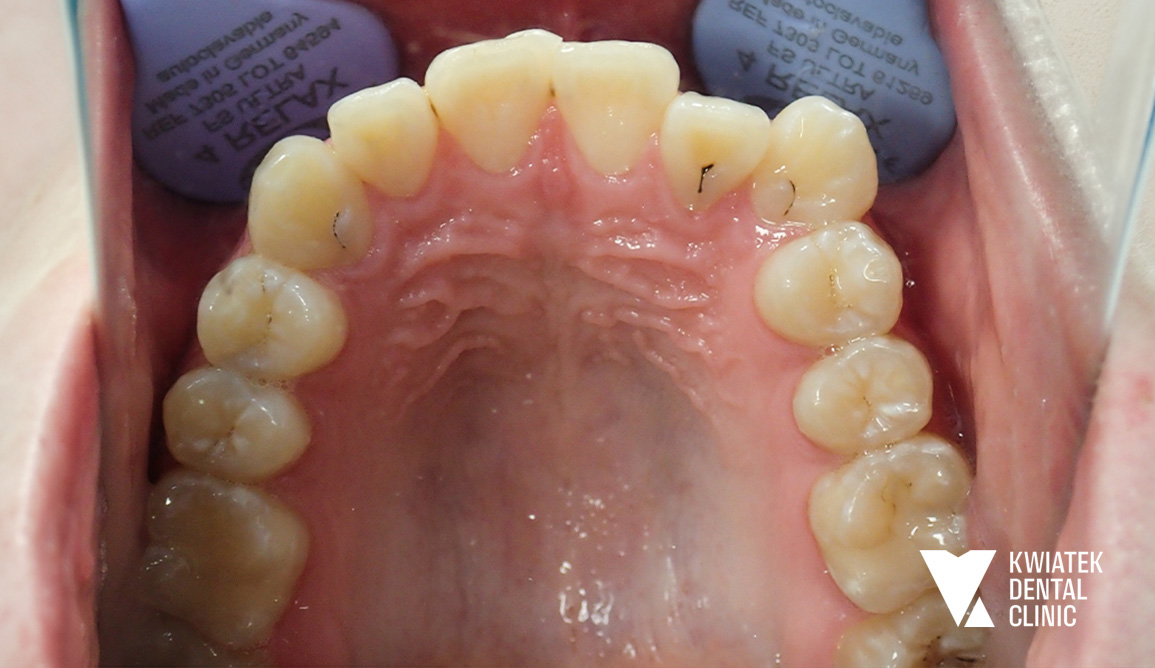

PRZED

PO

• zgryz krzyżowy zęba 12

• znaczny deficyt miejsca dla zębów 12 i 13

• wychylenie przedsionkowe zęba 13

Uzyskano prawidłowe ustawienie zębów w łukach, korektę zgryzu krzyżowego, właściwą relację zgryzową oraz harmonijną estetykę uśmiechu. Metamorfoza pokazuje, jak dzięki dokładnej diagnostyce, nowoczesnym technikom ortodontycznym oraz konsekwentnemu prowadzeniu leczenia można osiągnąć stabilny i naturalny efekt bez konieczności usuwania zębów przedtrzonowych.